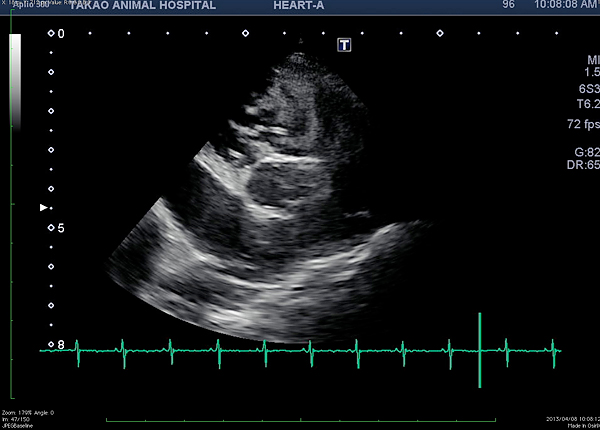

フィラリアとは蚊から媒介され、肺や心臓に寄生する虫です。フィラリアの寄生により肺炎や肺動脈塞栓などを起こし、 その結果、肺高血圧症を引き起こします。月に1度の予防薬の投薬で予防できます。最近では猫の感染報告も増えてきました。 フィラリア症になると完治させる方法がありません。きちんとした予防が必要です。当院では猫のフィラリア症予防も行っています。

• フィラリアによるベナケバシンドローム(右心房内のフィラリア虫体)